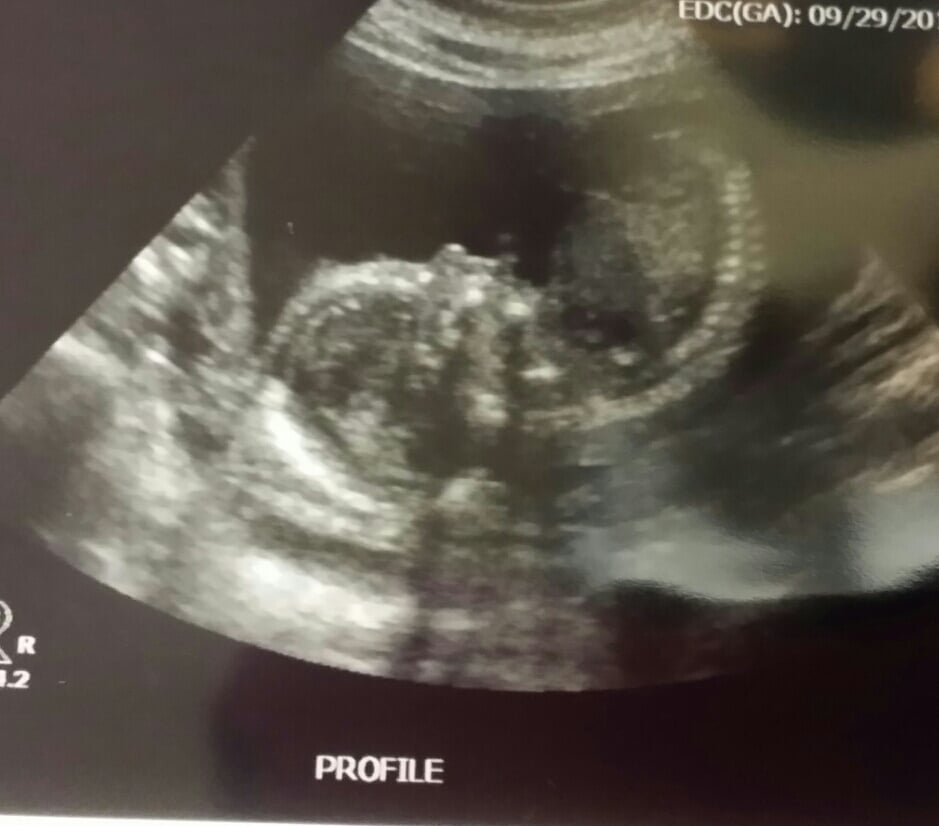

Here is one of the photos we got of Miss AB:

When we got to the appointment and the ultrasound tech started our scan none of us could believe how active she was in there. It was like she was having a dance party and she was just dancing away. It took the ultrasound tech longer than normal to get all of the measurements that she needed.

After the ultrasound tech finished, the High Risk OB came in and took a few measurements of her own. There was one concern where her kidneys looked bigger than normal but they measured "normal".

At the end the doctor said everything looked great and we got released from having to see the high risk OB anymore -- so long as my blood pressure continues to cooperate.